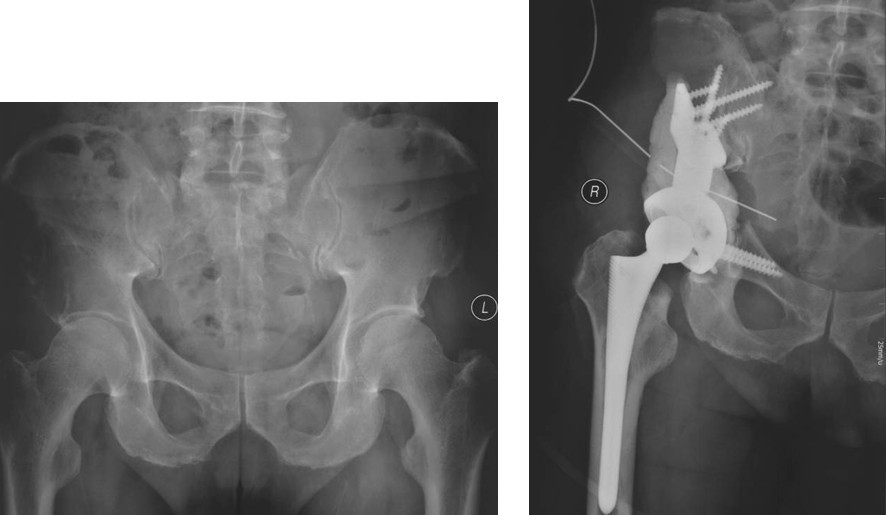

Ⅳ型:为了达到治愈而需要进行整块的髋臼切除。对于部分单一髋臼转移的病例,以及髋臼周围骨质破坏范围较大的病变,在广泛切除肿瘤后,重建髋关节(内半盆切除)有时较为困难。在这些病例,可以选择马鞍式假体。这种方法最开始用于全髋关节置换术后的骨缺损,后来也用于原发或转移性髋臼肿瘤的治疗。也可以选用带有固定翼,能固定于残存髂骨和耻骨支的定制型髋臼假体(7-9)。这种假体制作前通常需要进行CT模拟重建设计。固定方式常用螺丝钉和骨水泥。有时想要应用定制型假体达到理想的固定位置较为困难。对于骨盆环的完整性重建,纵向稳定是极其重要的,同时要考虑人工假体在术中的可操作性。定制型骨盆假体为非组配式,其髂骨固定螺钉是单轴向的,不能根据术中截骨情况调整假体,固定也不够牢固。 我们设计使用的可调式半骨盆假体,其髂骨固定钉改为双轴向或多轴向固定,假体与骨之间的界面为垂直压力、而非剪力,增加了稳定性,同时可以根据髂骨截骨的高度选择颈长的臼杯,利于安装和保持骨盆平衡(10)。组配式骨盆假体还考虑到骨盆纵向和侧方的稳定因素, 尽量达到恢复骨盆环连续性和稳定性的目的。对于髂骨区和髋臼上缘的骨缺损重建,钉棒系统简单,易于操作,但固定钉在骨内的应力较大,容易在负重的情况下对骨质产生切割,尤其骨质疏松的病人固定更加不稳,因此需用骨水泥加强。由于组配式人工骨盆是一个组合装置,因而体积较小,便于软组织覆盖,伤口感染率大大下降。

图5,男,69岁,肾癌髋臼转移, Harrington IV型